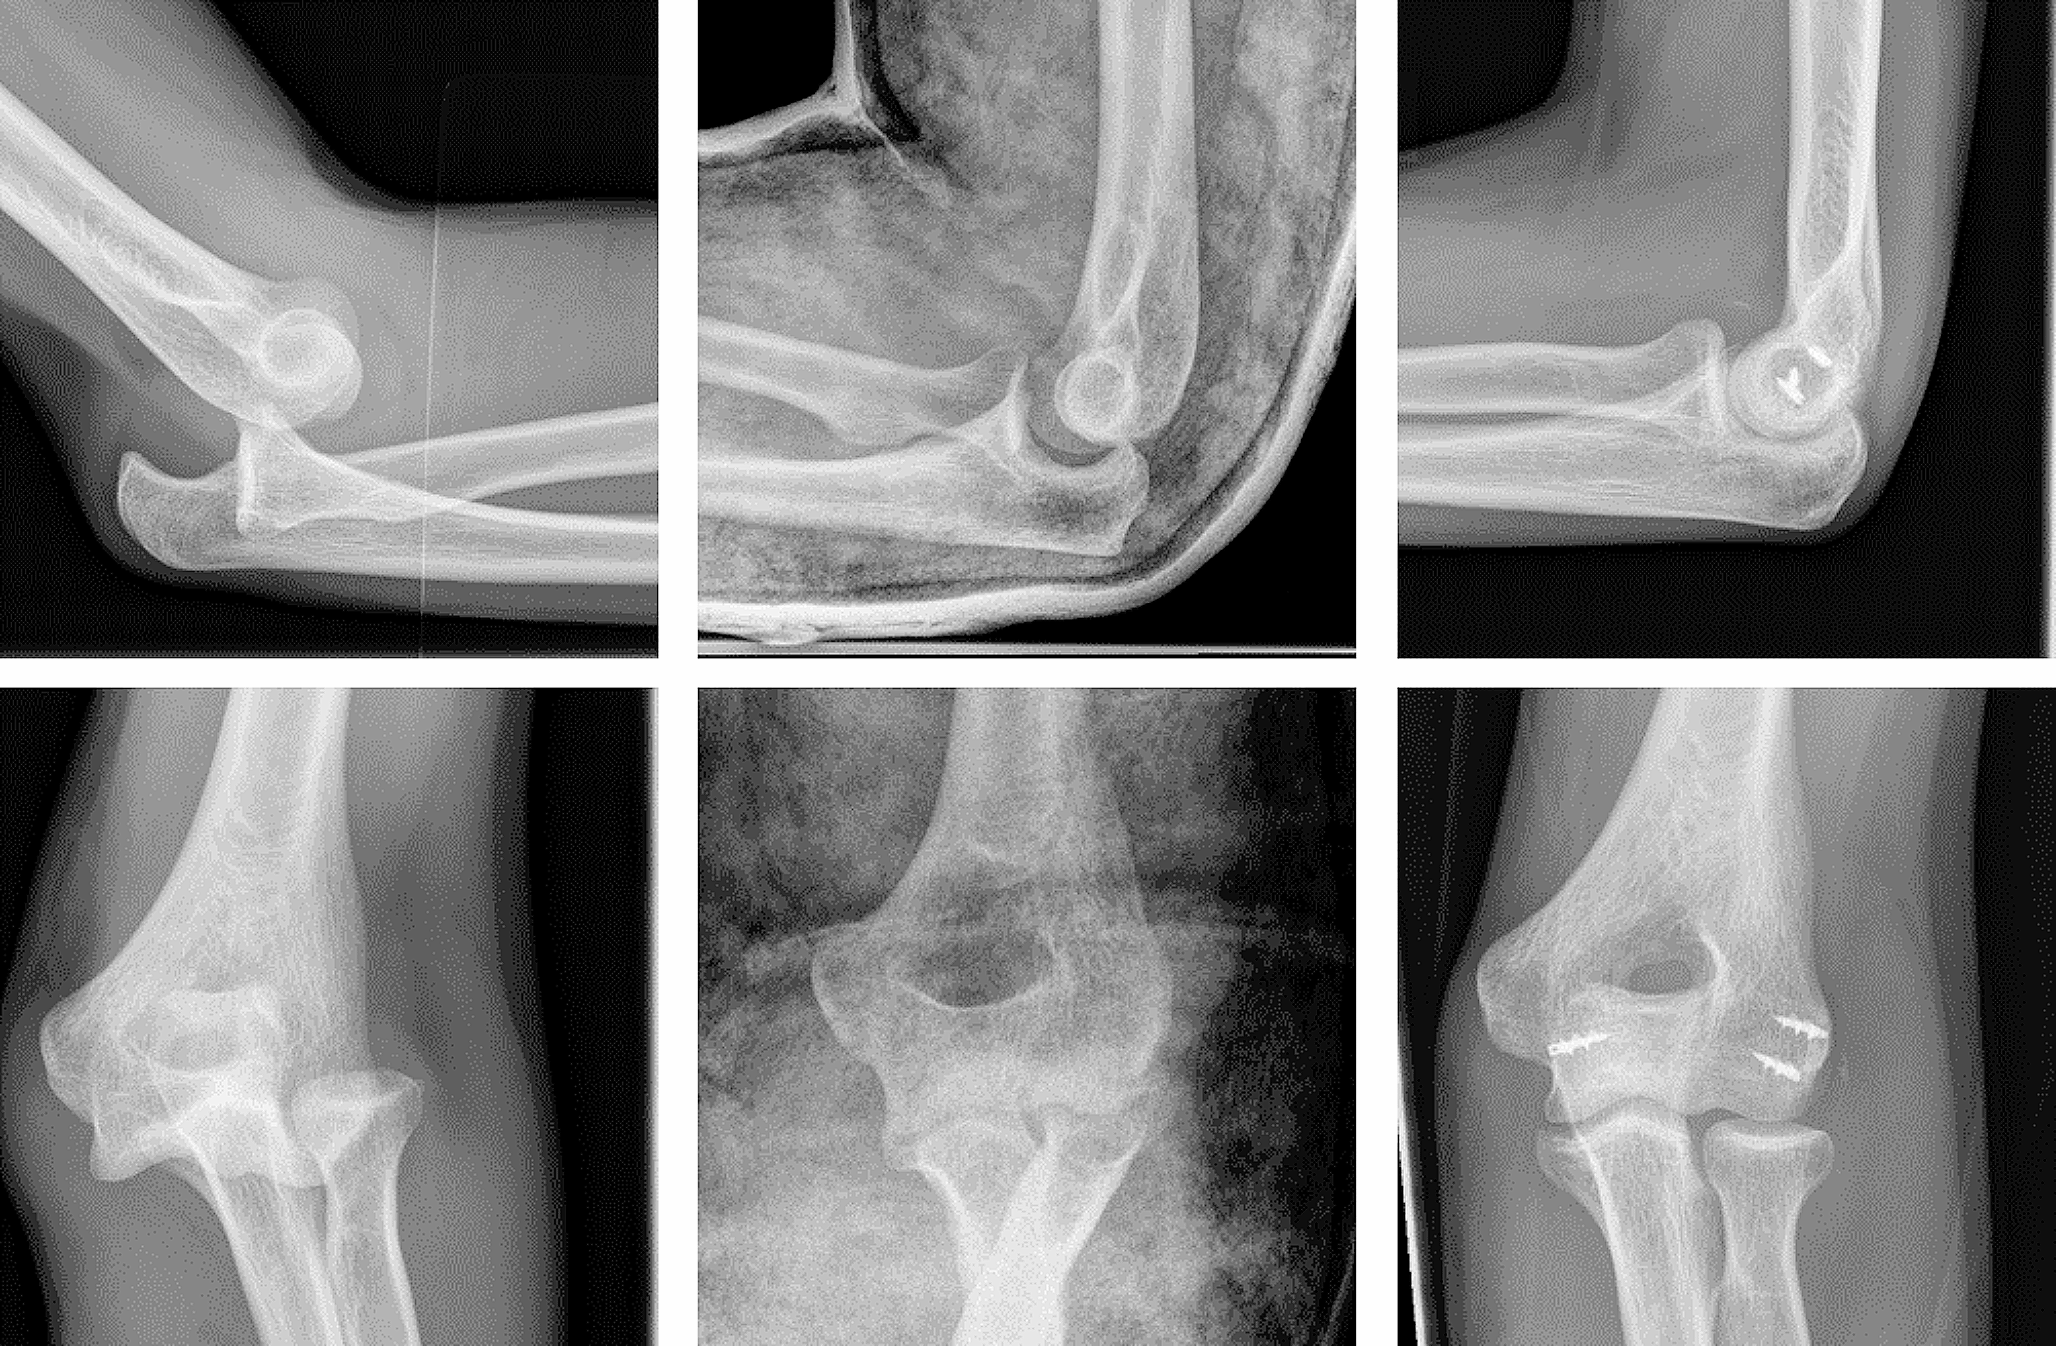

Figure 1 shows exemplary radiographs of acute dislocations prior to and after reduction as well as the postoperative results.

Fig. 1

x-ray diagnostics: left acute posterior elbow dislocation after fall in bouldering; middle: drop sign indicating persisting instability after reduction; right: postoperative results after capsular-ligament reconstruction of the radial and ulnar collateral ligament and the common extensor origin